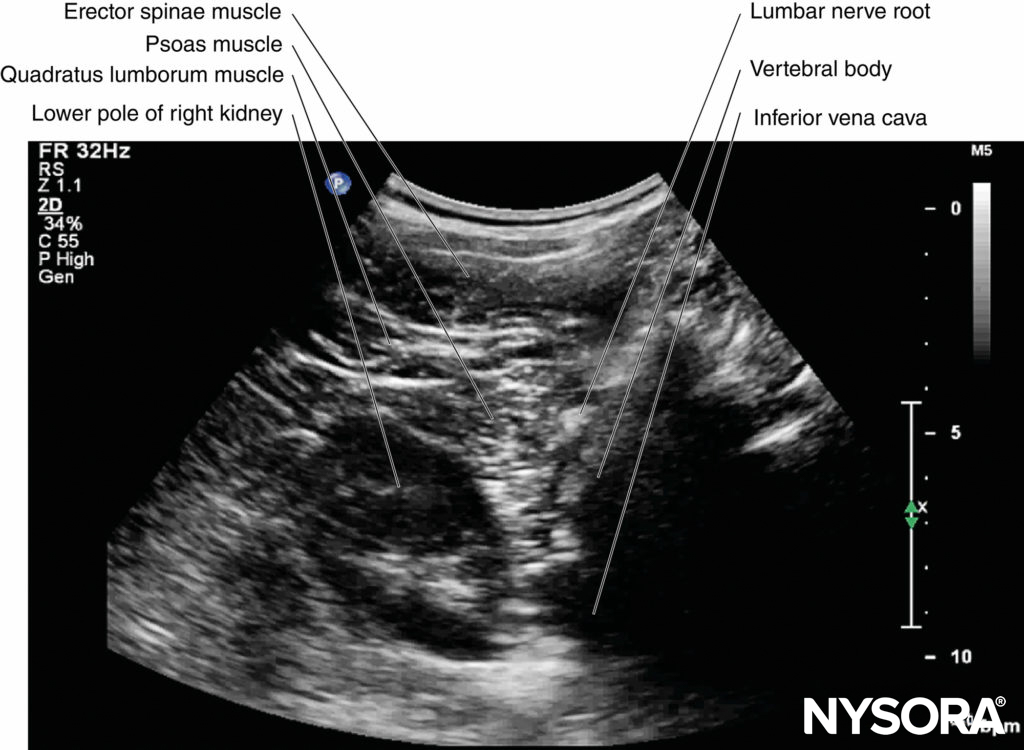

Nevertheless, the nerves of the lumbar plexus can be differentiated from the intramuscular tendons as they are thicker than the muscle fibers, take an oblique course through the psoas muscle (see Figure 11), and are better visualized after local anesthetic injection. A laterally positioned US transducer will produce a “suboptimal” sagittal sonogram without the US “trident,” but with the lower pole of the kidney, which lies anterior to the quadratus lumborum muscle and can reach the L3–L4 level in some patients.

Transverse Sonoanatomy

Kirchmair and colleagues were the first to describe the detailed transverse sonoanatomy of the lumbar paravertebral region relevant for LPB. However, they were unable to delineate the lumbar plexus in the cadavers and volunteers they examined, which they attributed to a loss of spatial resolution due to the use of low-frequency US. The author’s group has recently demonstrated that it is possible to accurately delineate the lumbar nerve root, lumbar paravertebral space, lumbar plexus, and psoas compartment using a paramedian transverse oblique scan (describe earlier).

On a typical PMTOS-TP (see Figure 10b), the erector spinae muscle, transverse process, psoas major muscle, quadratus lumborum muscle, and anterolateral surface of the vertebral body are clearly visualized (see Figure 13).

The psoas muscle appears hypoechoic, but multiple areas of hyperechogenicity are also interspersed within the central part of the muscle (see Figure 13). These hyperechoic speckles represent the intramuscular tendon fibers of the psoas muscle and are more pronounced below the level of the iliac crest.

The inferior vena cava (IVC; on the right side) and the aorta (on the left side) are also identified anterior to the vertebral body (see Figure 13) and are useful landmarks to look out for while performing a PMTOS. The lower pole of the kidney, which can extend to the L3–L4 level, is closely related to the anterior surfaces of the quadratus lumborum and psoas muscles and frequently seen as an oval structure that moves synchronously with respiration in the retroperitoneal space (Figure 21). The acoustic shadow of the transverse process obscures the posterior aspect of the psoas muscle during a PMTOS-TP (see Figure 13). Therefore, the lumbar nerve root and lumbar plexus are rarely visualized through the PMTOS-TP scan window. However, the spinal canal, with the dura and the intrathecal space, may be visualized during a PMTOS-TP (see Figure 13) due to the US signal entering the spinal canal through the interlaminar space (see Figure 13). Being able to visualize the neuraxial structures during a lumbar paravertebral scan may be useful in documenting epidural spread after an LPB.

FIGURE 21. Paramedian transverse oblique scan of the right lumbar paravertebral region through the intertransverse space and at the level of the articular process (PMTOS-AP). The lumbar nerve root is seen emerging from the intervertebral foramen. Also note that the lower pole of the right kidney is seen anterior to the psoas muscle in this sonogram.

In contrast, during a PMTOS through the lumbar intertransverse space and at the level of the articular process (PMTOS-AP) (see Figure 10c), apart from the erector spinae, psoas, and quadratus lumborum muscles, the intervertebral foramen, articular process, and lumbar nerve root are clearly delineated (see Figure 14). The LPVS is also seen as a hypoechoic space adjacent to the intervertebral foramen (see Figure 14), and the lumbar nerve root can be seen exiting the foramen to enter the paravertebral space (see Figure 14).

After it exits the intervertebral foramen, the lumbar nerve root does not enter the psoas muscle directly opposite the intervertebral foramen from which it emerges (see Figure 14), but takes a steep caudal course (see Figure 14), entering the psoas muscle at the vertebral level below to join the lumbar plexus. The lumbar plexus is seen as a separate hyperechoic structure within a hypoechoic space, the psoas compartment, in the posterior aspect of the psoas muscle (see Figure 14). In a transverse sonogram produced by the shamrock method (see Figure 15), the psoas, erector spinae, and quadratus lumborum muscles are also clearly visualized (see Figures 16, 17, 18 and 19). The anatomical arrangement of the three muscles around the transverse process—that is, the psoas muscle lying anteriorly, the erector spinae muscle lying posteriorly, and the quadratus lumborum muscle lying at the apex (see Figure 16)—produces a sonographic pattern that has been likened to the shape of a “shamrock,” with the muscles representing its three leaves. The lumbar nerve root may also be visualized close to the angle between the vertebral body and the transverse process (see Figure 16) and the lumbar plexus within the posterior aspect of the psoas muscle, typically about 2 cm anterior to the transverse process (see Figures 17 and 18). From this position, if the transducer is gently tilted caudally, the acoustic shadow of the L4 transverse process disappears, and the US beam is now insonated through the intertransverse space and at the level of the articular process of the L4 vertebra, similar to that seen with a PMTOS-AP (see Figure 17). As a result, apart from the psoas, erector spinae, and quadratus lumborum muscles, the intervertebral foramen and lumbar plexus may also be visualized (see Figure 17).